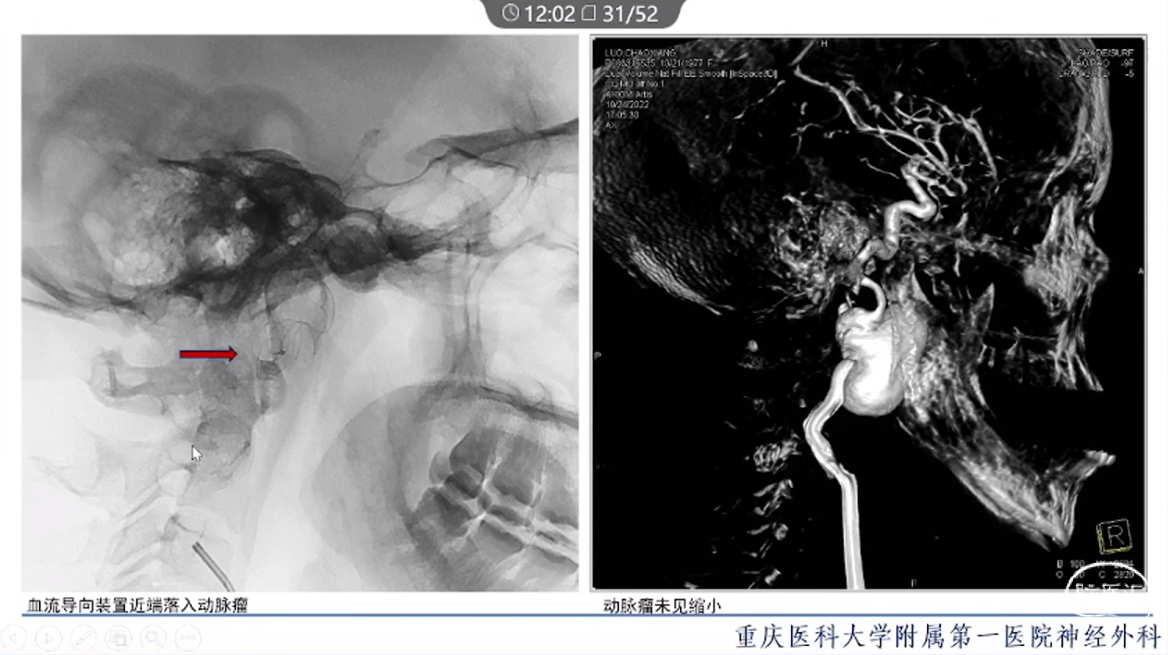

·颈内动脉颈段动脉瘤治疗方式有血管内治疗、外科手术和保守治疗。

·血管内治疗是最常见的治疗方式,随着血管内介入技术的发展和材料的进步,越来越多的动脉瘤可以通过血管内途径治疗。

·对于血管扭曲、血管直径大以及存在抗血小板禁忌的动脉瘤患者,特别是对于颈段大型或巨大型动脉瘤的治疗,常需要外科手术治疗。